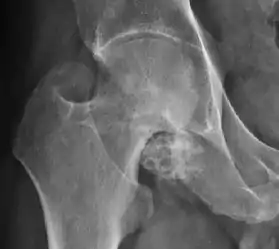

Synovial chondromatosis can be confidently diagnosed by X-ray when calcified cartilaginous chondromas are seen. However, other synovial proliferative processes, such as pigmented villonodular synovitis, require MRI for accurate diagnosis, although noncalcified synovitis can be suspected in radiographs by indirect signs, such as soft tissue swelling and/or erosions in the femoral head, femoral neck, or acetabulum (Figure 7).[1]

X-ray of synovial chondromatosis.[1]

CT of synovial chondromatosis.[1]

In synovial proliferative disorders, MRI demonstrates synovial hypertrophy. In the case of PVNS, characteristic foci of low signal intensity related to hemosiderin deposition are better seen on gradient echo T2* images (Figure 7). In the case of synovial osteochondromatosis, the synovial hypertrophy is accompanied by intermediate signal cartilaginous loose bodies and/or low signal calcified loose bodies.[1]

Computed Tomography

Due to radiation concerns, CT has been relegated after MRI in the study of intra-articular causes of hip pain. The only exception where CT is considered superior to MRI is in bone tumors, because of its ability in characterizing matrix calcifications, and in depicting the anatomy of acute traumatic fractures. Typical matrix calcifications include the following: (a) osteoid mineralization, like a dense cloud, (b) chondroid calcification, reproducing a punctate popcorn pattern, or (c) fibrous calcification, ground glass-like appearance. There are also tumors that typically do not show matrix calcification. CT is also used for accurate localization of the nidus in osteoid osteomas and this must be differentiated from Brodie’s abscess or a stress fracture. The current standard treatment of osteoid osteoma is percutaneous radiofrequency ablation and this is usually performed under CT guidance.[1]